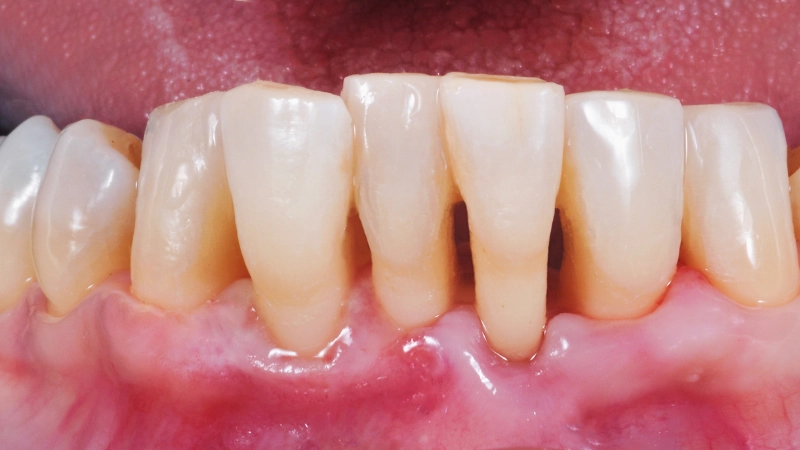

1 - Viêm lợi

- Nguyên nhân: Viêm lợi xảy ra khi mảng bám và vi khuẩn tích tụ dưới viền lợi gây ra viêm nhiễm. Ngoài ra, việc thay đổi hormone trong quá trình mang thai, mãn kinh, hoặc dùng một số loại thuốc cũng có thể là nguyên nhân.

- Tác hại: Viêm lợi nếu không điều trị kịp thời có thể tiến triển thành viêm nha chu, gây mủ, tụt lợi, làm răng lung lay và thậm chí mất răng.

5 - Viêm nha chu

- Nguyên nhân: Viêm nha chu xảy ra khi mảng bám không được làm sạch, vi khuẩn lây lan gây viêm ở nướu, xương ổ răng, và dây chằng nha chu.

- Tác hại: Viêm nha chu không được điều trị có thể dẫn đến tiêu xương ổ răng, làm răng lung lay và gây mất răng.